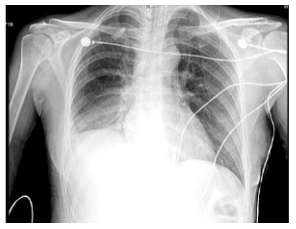

治疗6天后,患者右肺复张,直至转科前,患者肺部未出现任何问题(图5,图6)。于我科有创机械通气30天,未出现呼吸机相关性肺炎。

图5 患者治疗6天后胸部X线片